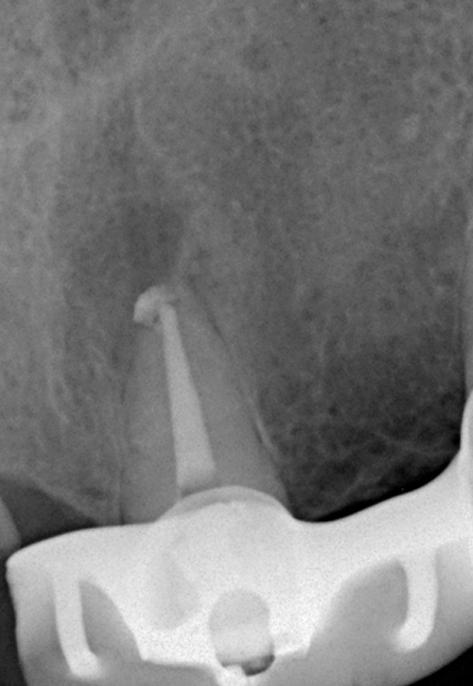

В связи с наличием у пациента жалоб и клинических симптомов принято решение о проведении ревизии корневого канала 21 зуба. Проведена терапия с помощью гидроокиси кальция в течении 4-х недель (снимок 3). Пломбировка канала гуттаперчей и корневым герметиком.